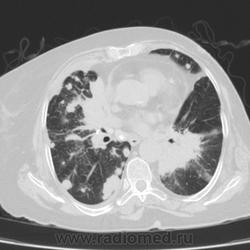

Метастатическое поражение легких.

Пожилая женщина, 76 лет находится на стац.лечении, провели СКТ дообследование.  Сопут- сr левой молочной железы. Такие множественные

поражения  в легких встречаются не часто.

Раннее несколько лет назад оперирована по поводу рака левой молочной железы.